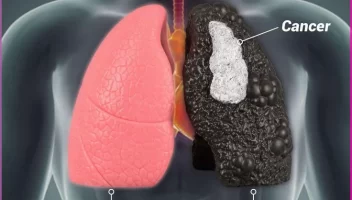

علاج سرطان الرئة

→ العودة لدليل السرطان علاج سرطان الرئة في الأردن: وداعاً للكيماوي في كثير من الحالات هل تعلم أن سرطان الرئة أصبح يعالج بـ “حبوب ذكية” في المنزل؟ اكتشف الطفرات الجينية التي غيرت قواعد اللعبة. لم يعد التشخيص “حكماً بالإعدام” لسنوات طويلة، كان سرطان الرئة يعني خياراً واحداً: جلسات كيماوي منهكة. اليوم، الصورة مختلفة تماماً في […]